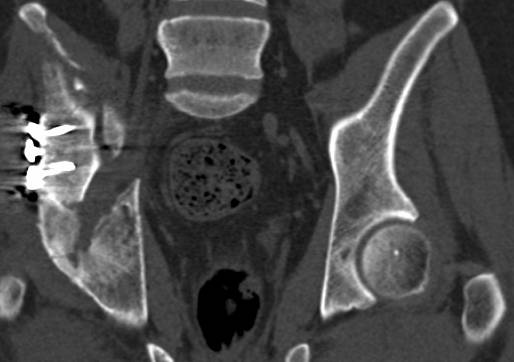

[Ortho] перелом правой половины таза

высылаю дополнительно  сканы.